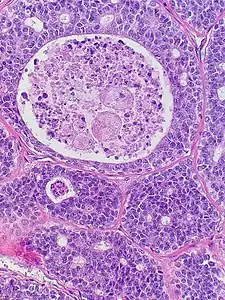

Histopathological image of adenoid cystic carcinoma of the salivary gland infiltrating a nerve (center), H&E stain

Adenoid cystic carcinoma with comedonecrosis